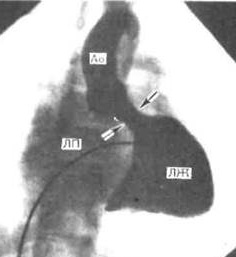

В настоящее время наиболее доступным, простым, безболезненным для ребенка и высокоинформативным методом диагностики пороков сердца является эхокардиография. Во время исследования с помощью ультразвукового датчика врач видит толщину стенок, размеры камер сердца, состояние клапанной системы и расположение крупных сосудов. Допплеровский датчик позволяет увидеть направления кровотока и измерить его скорость. Во время исследования можно выполнить снимки, подтверждающие заключение специалиста. Также ребенку обязательно запишут электрокардиограмму. При необходимости более точного исследования (как правило, для определения тактики хирургического лечения порока) врач порекомендует зондирование сердца. Это инвазивная методика, для выполнения которой ребенок госпитализируется в стационар. Зондирование проводится врачем-рентгенхирургом в рентгеноперационной, в присутствии врача-анестезиолога, под внутривенным наркозом. Через прокол в вене или артерии специальные катетеры вводятся в сердце и магистральные сосуды, позволяя точно измерить давление в полостях сердца, аорте, легочной артерии. Введение специального рентген-контрастного препарата позволяет получить точное изображение внутреннего строения сердца и крупных сосудов (см. рисунок).